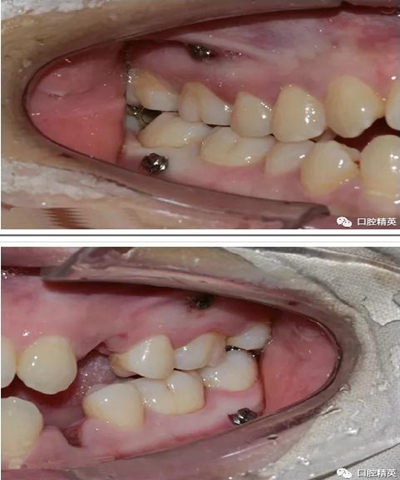

微型種植釘直徑僅有1.6mm和2mm,植入部位幾乎可以不受限制,可植入牙槽骨的任何部位,微型種植體支抗植入手術(shù)操作簡單、安全,不需要牙齦翻瓣,即可旋入微型種植體,整個(gè)手術(shù)過程僅需5-10min,術(shù)后患者的不良反應(yīng)少,微型種植體的取出亦非常簡單,甚至不需局部麻醉,將其反向旋出即可。自攻型種植釘植入牙槽骨中起支抗作用.

一般情況下是成年人使用,特殊病例十三、四歲的小孩可以用。種植釘可以打在牙槽骨的任何部位??梢栽?個(gè)牙齒之間的牙槽骨上打釘,或者打在頰側(cè)牙槽骨與牙根之間,主要看你是如何應(yīng)用支抗了。2個(gè)牙齒之間的牙槽骨上打釘,支抗作用拉動(dòng)的牙齒有限,而打在頰側(cè)牙槽骨與牙根之間可以將整個(gè)牙列拉向遠(yuǎn)中移動(dòng)。種植支抗釘在矯正結(jié)束后要拿下來。

再次,植入微型種植體,在附著牙齦處不需要粘骨膜翻瓣,在牙槽黏膜處則需要切開黏膜以避免植入時(shí)軟組織被卷入,植入部位通常在膜齦結(jié)合部位或偏根方2~3mm,植入角度與骨面垂直并傾斜15~20度,即向根尖方向植入,術(shù)后拍根尖片以確認(rèn)與牙根的關(guān)系。術(shù)后口服抗生素預(yù)防感染并進(jìn)行口腔衛(wèi)生宣教。

上頜種植釘?shù)闹睆?.6,長度11mm;下頜直徑2.0,長度9mm

1、上頜種植釘常見位置在5,6之間;下頜種植釘常見位置在6,7之間。